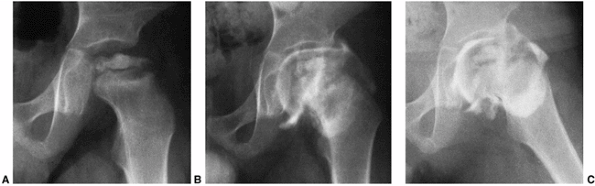

Figure 25.8 A boy, 4 years and 9 months of age, with Catterall group 4 disease and at-risk status. A: Plain radiograph. B:

Arthrogram in neutral abduction, adduction, and rotation. There is enlargement and flattening of the cartilaginous femoral head, and the lateral margin of the acetabulum is deformed by the femoral head. C: Arthrogram in abduction and slight external rotation. The femoral head hinges on the lateral edge of the acetabulum, further deforming the lateral acetabulum. Slight pooling of dye is seen medially. Note that the widened joint space is an apparent widening, not a real widening, and that it is secondary to continued growth of the superficial zone of cartilage in the absence of growth of the ossific nucleus. |